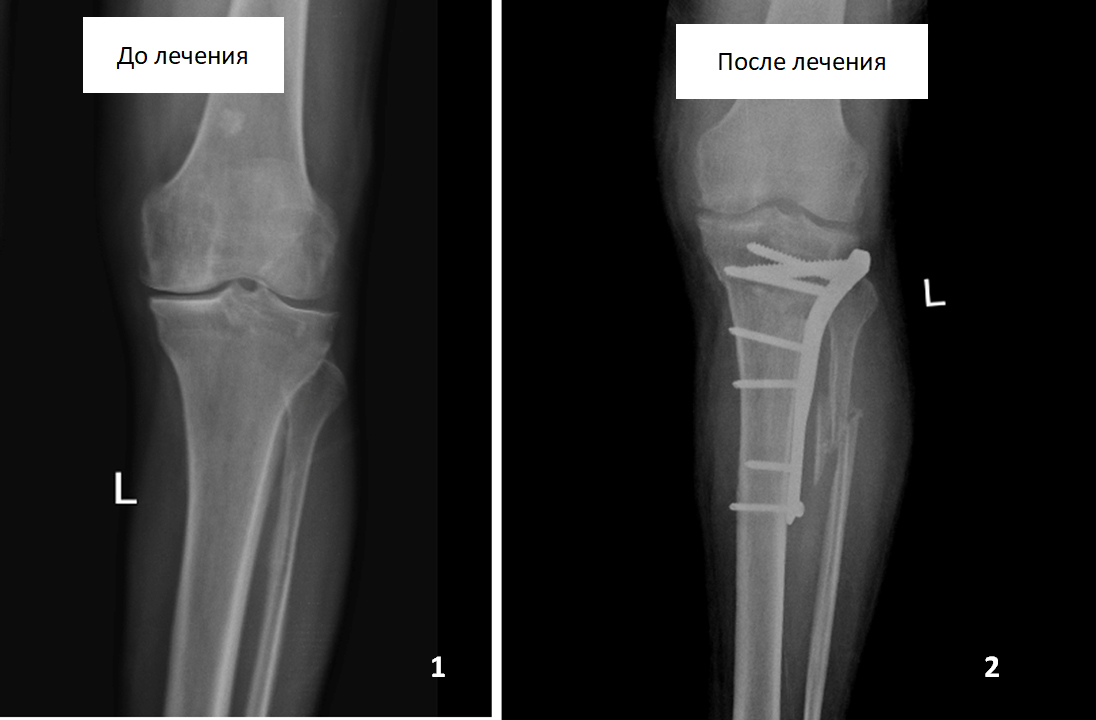

Пациент 63 лет, обратился за помощью с жалобами в области левой голени и левого коленного сустава. Во время консультаций в других медицинских учреждениях пациенту было предложено выполнить протезирование левого коленного сустава, от которого он отказался. При обследовании нами была выявлена установочная варусная деформация левой голени (см. фото 1) и выполнена корригирующая резекция левой большеберцовой кости, в результате которой ось кости была восстановлена (см. фото 2). В настоящее время боли в области левой голени и левого коленного сустава пациента не беспокоят, он полноценно пользуется конечностью в течение 2 лет после операции.